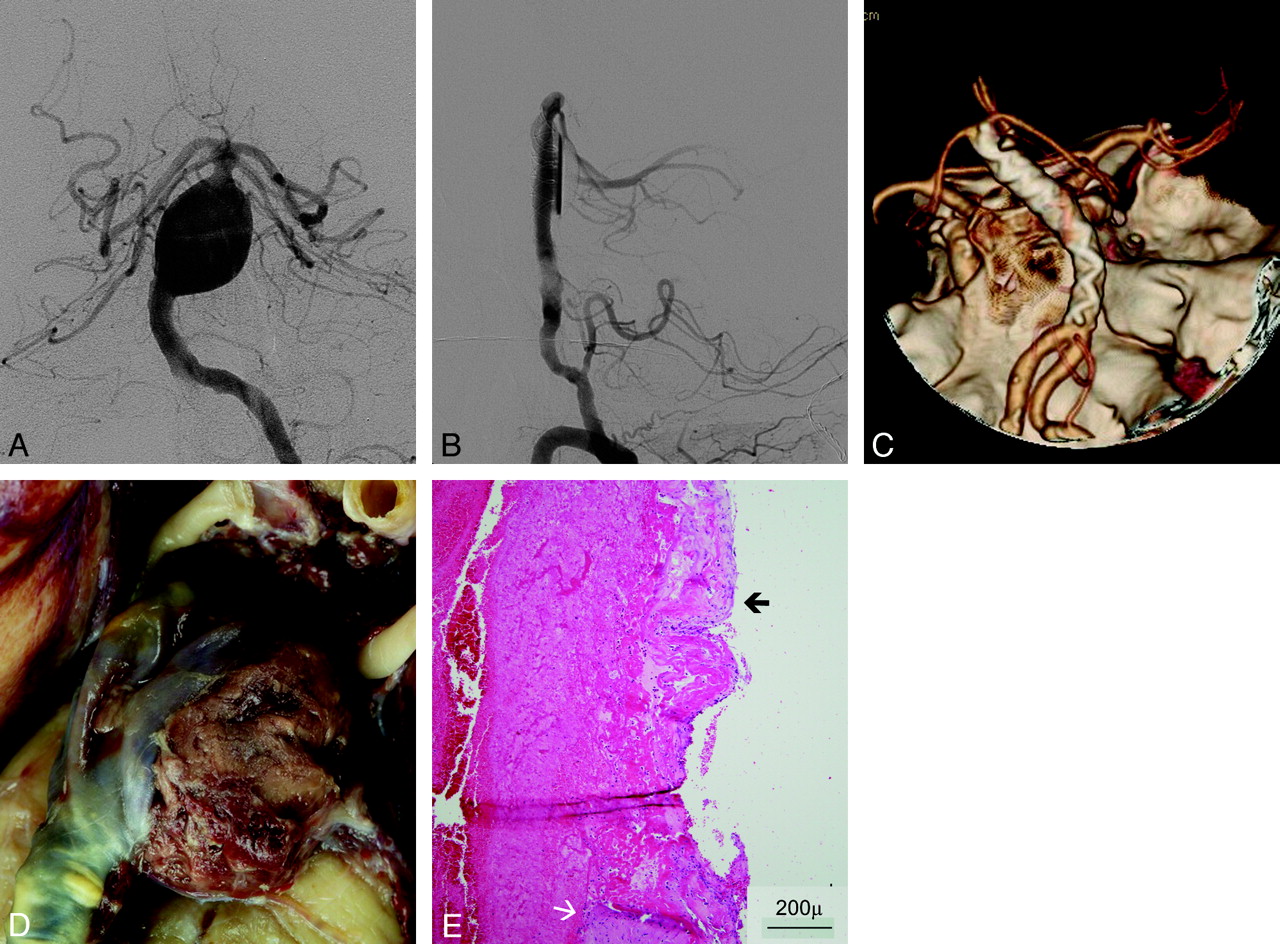

Pathology Results

Postmortem dissection and detailed histopathologic examination were performed in patients 5 and 6, showing a massive subarachnoid hemorrhage. Macroscopically, both aneurysms showed massive organizing intraluminal thrombus and mural thinning at the site of rupture (Fig 2). Microscopically, the aneurysm wall at the site of the rupture was extremely thin, with mural necrosis, loss of fibrous tissue and medial smooth muscle cells, and infiltration by macrophages extending from the adventitial surface (Fig 3).

Patient No. 6. A and B, Posteroanterior view DSA image of a symptomatic fusiform aneurysm of the basilar trunk (A) and lateral view after FD treatment (B) demonstrate contrast stasis in the aneurysm. C, 3D CT angiogram obtained 3 days after treatment shows patency of the basilar trunk and lack of aneurysm filling. D, Macroscopic view of the basilar artery and aneurysm after postmortem examination shows a massive thrombus volume bulging through the aneurysm wall defect. E, HE-stained microscopic view of the edge of the aneurysm wall rupture shows a partially maintained but vanishing adventitia (black arrow) and disappearance of the vascular tunica media (white arrow).